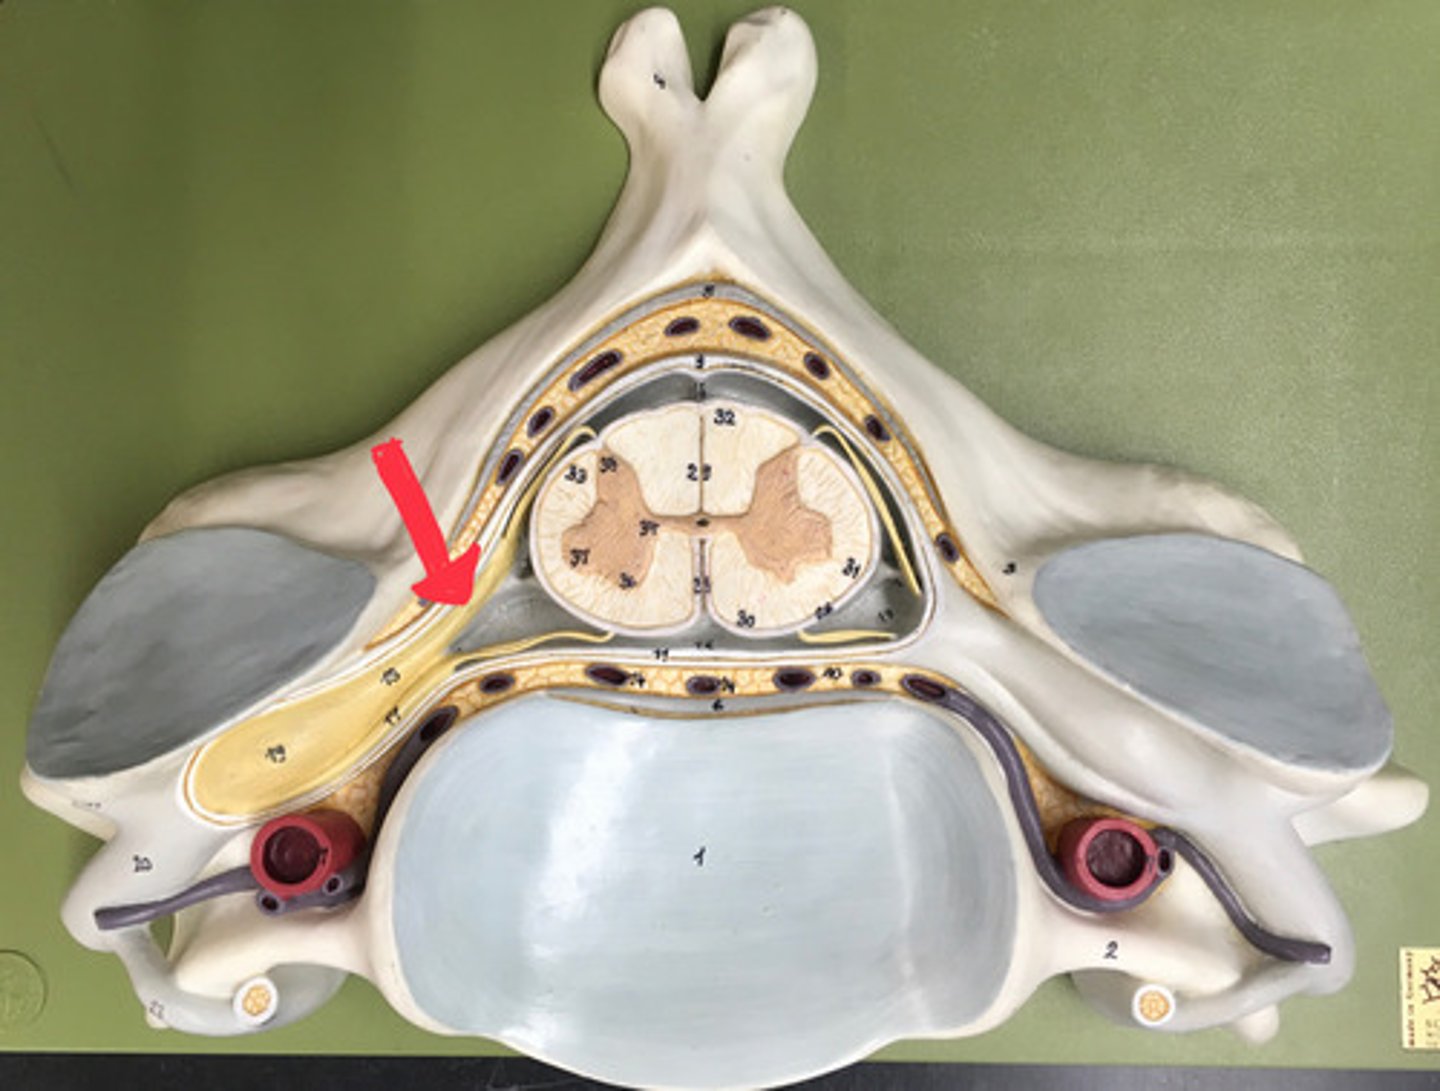

epidural space

dura mater

thick, outermost layer of the meninges surrounding and protecting the brain and spinal cord

subdural space

space between dura mater and arachnoid mater

arachnoid mater

middle layer of the meninges

B on model

subarachnoid space

a space in the meninges beneath the arachnoid membrane and above the pia mater that contains the cerebrospinal fluid

pia mater

the delicate innermost membrane enveloping the brain and spinal cord.

denticulate ligaments

extensions of pia mater that secure cord to dura mater laterally

posterior root

axons of sensory neurons

posterior root ganglion

anterior root

axons of motor neurons

spinal nerve